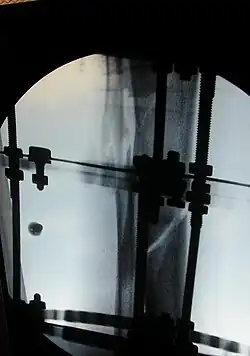

The photographs and radiographs illustrate the application and emplacement of an external fixator, an Ilizarov apparatus, to repair the open fracture of the lower left leg of a man. The photographs were taken four weeks after the patient fractured the shinbone (tibia) and the calfbone (fibula) of his left leg, and two weeks after the surgical emplacement of the Ilizarov apparatus to immobilise the leg and isolate the wound and fracture site to facilitate healing.

X-ray of the open fracture of the left leg; the external fixator was installed ca. 24 hrs. in hospital.

X-ray of the open fracture site immediately after installation of the Ilizarov apparatus.